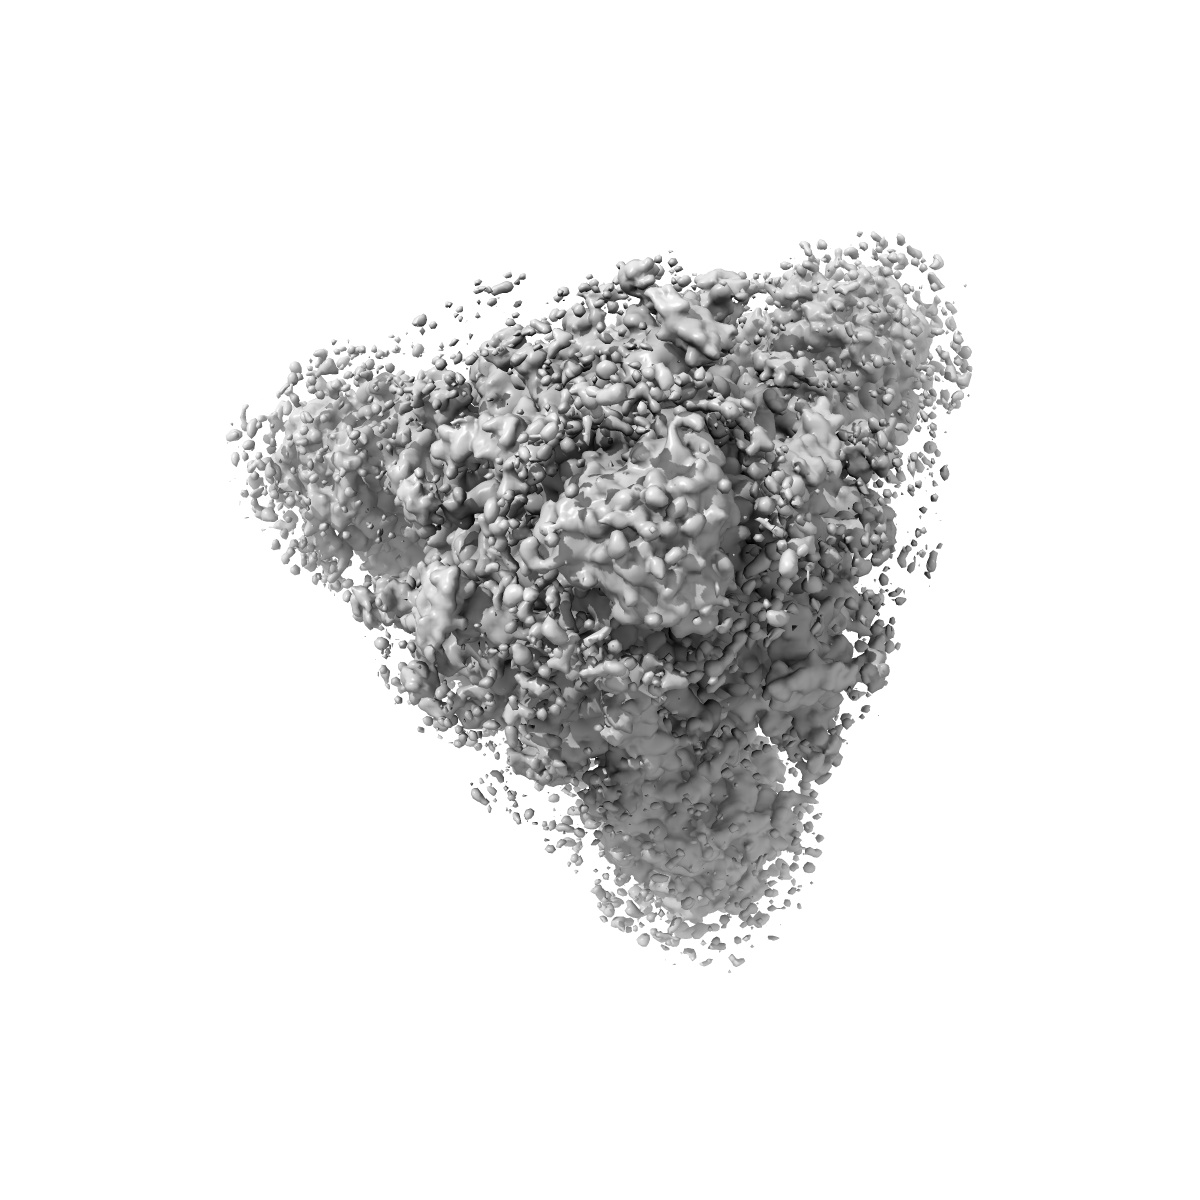

EMD-26021

Structural and functional impact by SARS-CoV-2 Omicron spike mutations

Single-particle3.1 Å

Sample: Closed state of pre-fusion SARS-CoV-2 Omicron variant spike protein